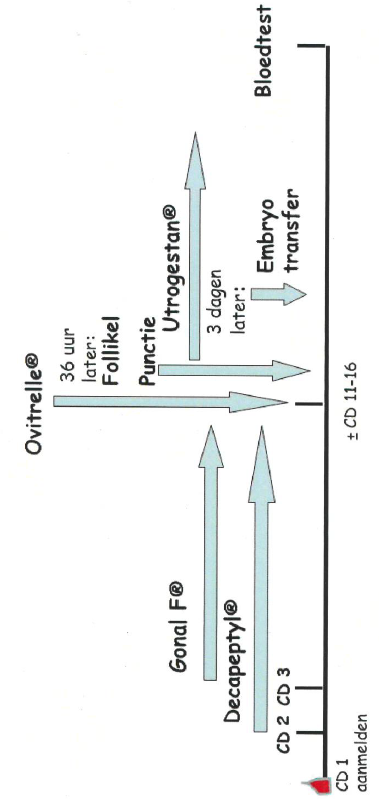

Het korte IVF- / ICSI-schema:

∆

zwangerschapstest

- Cyclusdag 1 (CD1): aanmelden

- Cyclusdag 2: eerste echo

- Cyclusdag 2: start Decapeptyl® injecties. Eenmaal daags één onderhuidse injectie. De Decapeptyl® injecties zijn enerzijds bedoeld om de eierstokken tot rust te brengen en anderzijds om de natuurlijke eisprong te onderdrukken. Hierdoor wordt voorkomen dat de eiblaasjes al vanzelf zijn verdwenen voordat de punctie plaatsvindt.

- Met de Decapeptyl® injecties gaat u door tot de eiblaasjes rijp zijn en de arts zegt dat u mag stoppen.

- Cyclusdag 3: start stimulatie van de eierstok(ken) met Gonal-F®. De dosering van de Gonal-F® heeft u bij de echo te horen gekregen. U gebruikt nu 2 injecties per dag, de Gonal-F® en de Decapeptyl®. Hiermee gaat u door totdat de eiblaasjes rijp zijn.

Het afsluiten van de stimulatiefase

Deze laatste stap is bij beide schema’s gelijk. Als bij echoschopisch onderzoek blijkt dat de eiblaasjes voldoende groot zijn en de hormoonspiegel van het Oestradiol in het bloed goed gestegen is, wordt de stimulatie afgerond door de toediening van de Ovitrelle ® injectie. Deze injectie zet de laatste rijpingsfasen van de eicel(len) in gang. Deze zeer belangrijke, onmisbare injectie sluit de stimlatiefase af en moet altijd ’s avonds op een afgesproken tijdstip worden toegediend. Ook deze injectie spuit de patiënt zelf.

Tussen de Ovitrelle ® injectie en de punctie zit 36 uur.